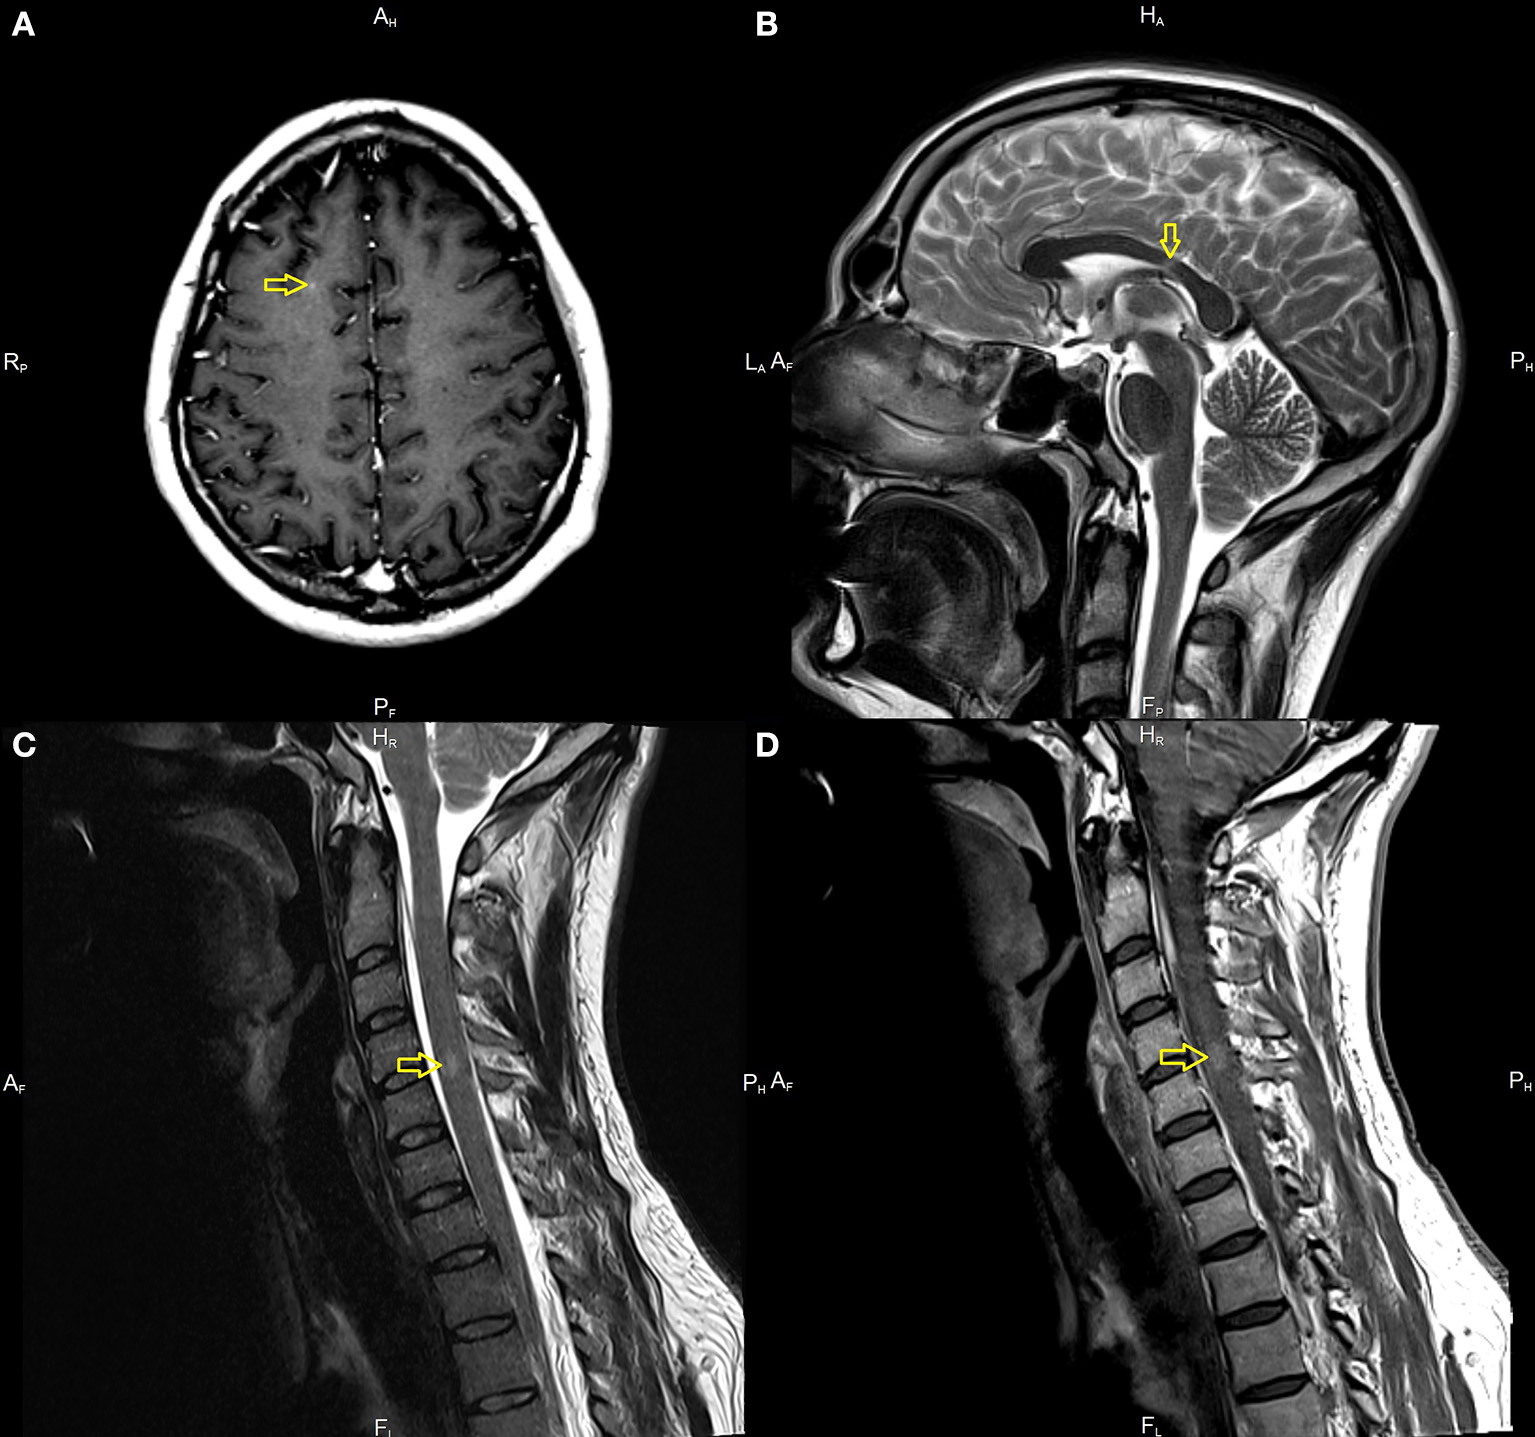

A 33-year-old male with a history of mild, well-controlled hypertension developed right upper and lower extremities numbness 2 weeks after receiving Johnson & Johnson's Janssen COVID-19 vaccine. In the prior period, the patient was not positive for coronavirus disease 2019 (COVID-19) infection and did not present any symptoms suggesting the presence of SARS-CoV-2 infection. Due to the above symptoms, the patient was admitted to the Department of Neurology. The examination revealed right side sensory impartment (loss of pain and temperature feeling) at the C5 level. Magnetic resonance imaging (MRI) scans of the brain and thoracic and cervical spine were performed. The brain MRI detected several demyelinating lesions, one with enhancement (in the subcortical region of the right frontal lobe). The spinal cord imaging showed an enhancing lesion consistent with demyelination at the fourth/fifth cervical vertebrae (C 4/5) and one smaller lesion at the level of the third/fourth cervical vertebrae (C3), without enhancement (Figure 1). Cerebrospinal fluid (CSF) analysis demonstrated moderate pleocytosis (25 leukocytes/μl; normal range 0–5 leukocytes/μl), elevated IgG index (0.84; normal range 0.0–0.7), and the presence of oligoclonal bands (serum unmatched CSF oligoclonal bands). Other evaluations from serum and CSF were unremarkable (serum: C-reactive protein, erythrocyte sedimentation rate, blood count were in the limits of the laboratory standard; CSF: glucose value 76 mg/dl with normal range of 50–80 mg/dl, protein value 44 mg/dl with normal range of 15–45 mg/dl). Diagnostic tests for infectious were negative. These included an examination of the presence of Borrelia burgdorferi and tick-borne encephalitis virus; the region of the patient living is endemic for both. Tests for the presence of anti-aquaporin-4 antibodies, myelin basic protein antibodies, and antibodies to myelin oligodendrocyte glycoprotein were negative. The evaluation for other autoimmune diseases was negative and included: rheumatoid factor, antiprothrombin, antinuclear, antiphospholipid, and antineutrophil cytoplasmic antibodies, antigens against :dsDNA, nucleosome, histosome, SS-A, Ro-52, SS-B, nRNP/Sm, Sm, Mi-2alfa, Mi-2beta, Ku, A, and B centromeres, Sp100, PML, PM-Scl100, PM-Scl75, Scl-70, RP155, gp210, PCNA, and DFS70.

Magnetic resonance imaging (MRI) in the described case of multiple sclerosis (MS). Demyelination lesions are marked with yellow arrows, respectively. (A) T1-weighted subcortical Lesion with gadolinium enhancement on brain MRI on axial sequences. (B) T2-weighted images showing lesion located in corpus callosum. (C) T2 hyperintense acute lesion on cervical spinal cord on sagittal sequences. (D) Gadolinium enhancement of a lesion located in the cervical spinal cord.